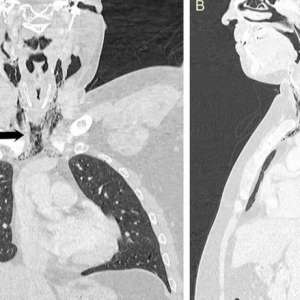

Мужчина испытал болезненные ощущения в области шеи, когда пытался сдержать чихание.

В результате чихания он ощутил «хлопок» в шее, после чего возникли проблемы с глотанием. МРТ-исследование показало, что воздух выходил через отверстие в трахее в мягкие ткани шеи. В течение нескольких дней мужчина получал питание через зонд, чтобы ткани могли зажить.

Когда мы сдерживаем чихание, воздух не может выйти наружу, и его давление разрывает мягкие ткани, причиняя им вред.